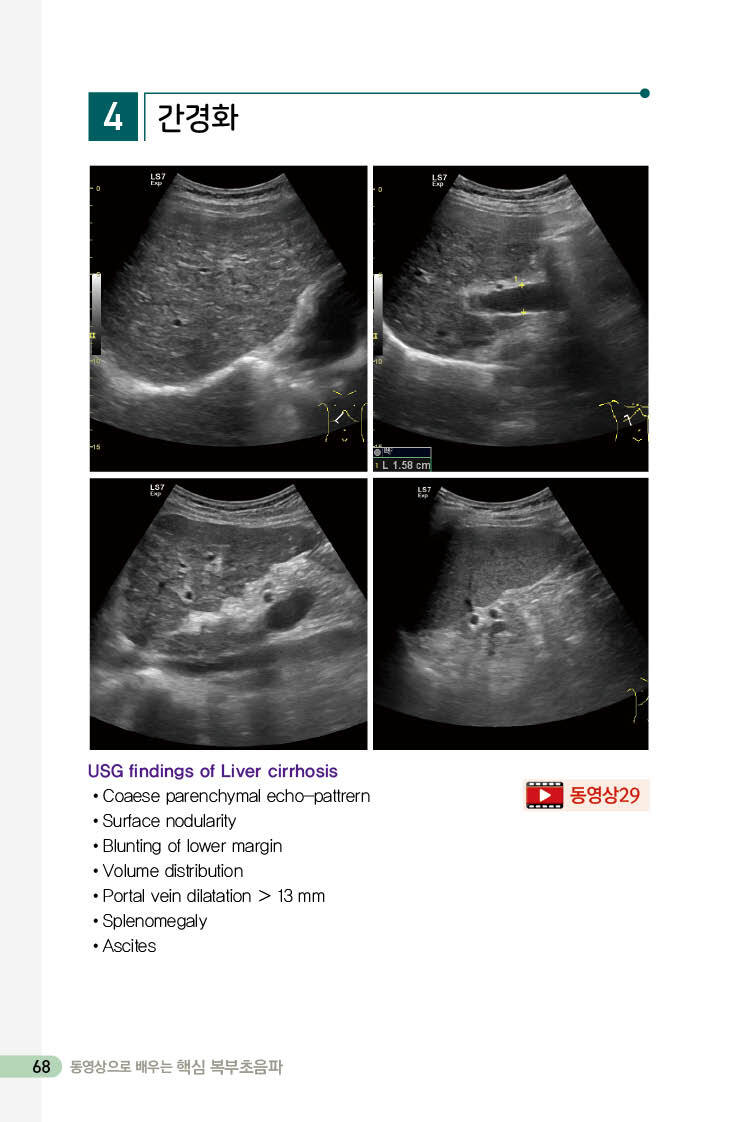

간경화 68